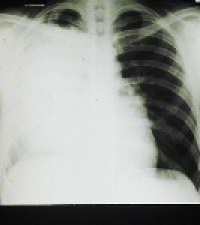

Recent research has shown low-dose computed tomography (LDCT) is beneficial in reducing deaths from lung cancer. So the AATS task force recommends an annual lung cancer screening using LDCT for: